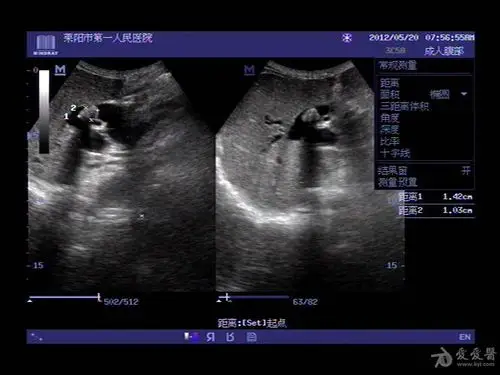

幽灵般的药物性胆囊结石

腹部超声 | 不典型胆囊结石——泥沙样结石

胆囊结石,胆囊炎的超声诊断